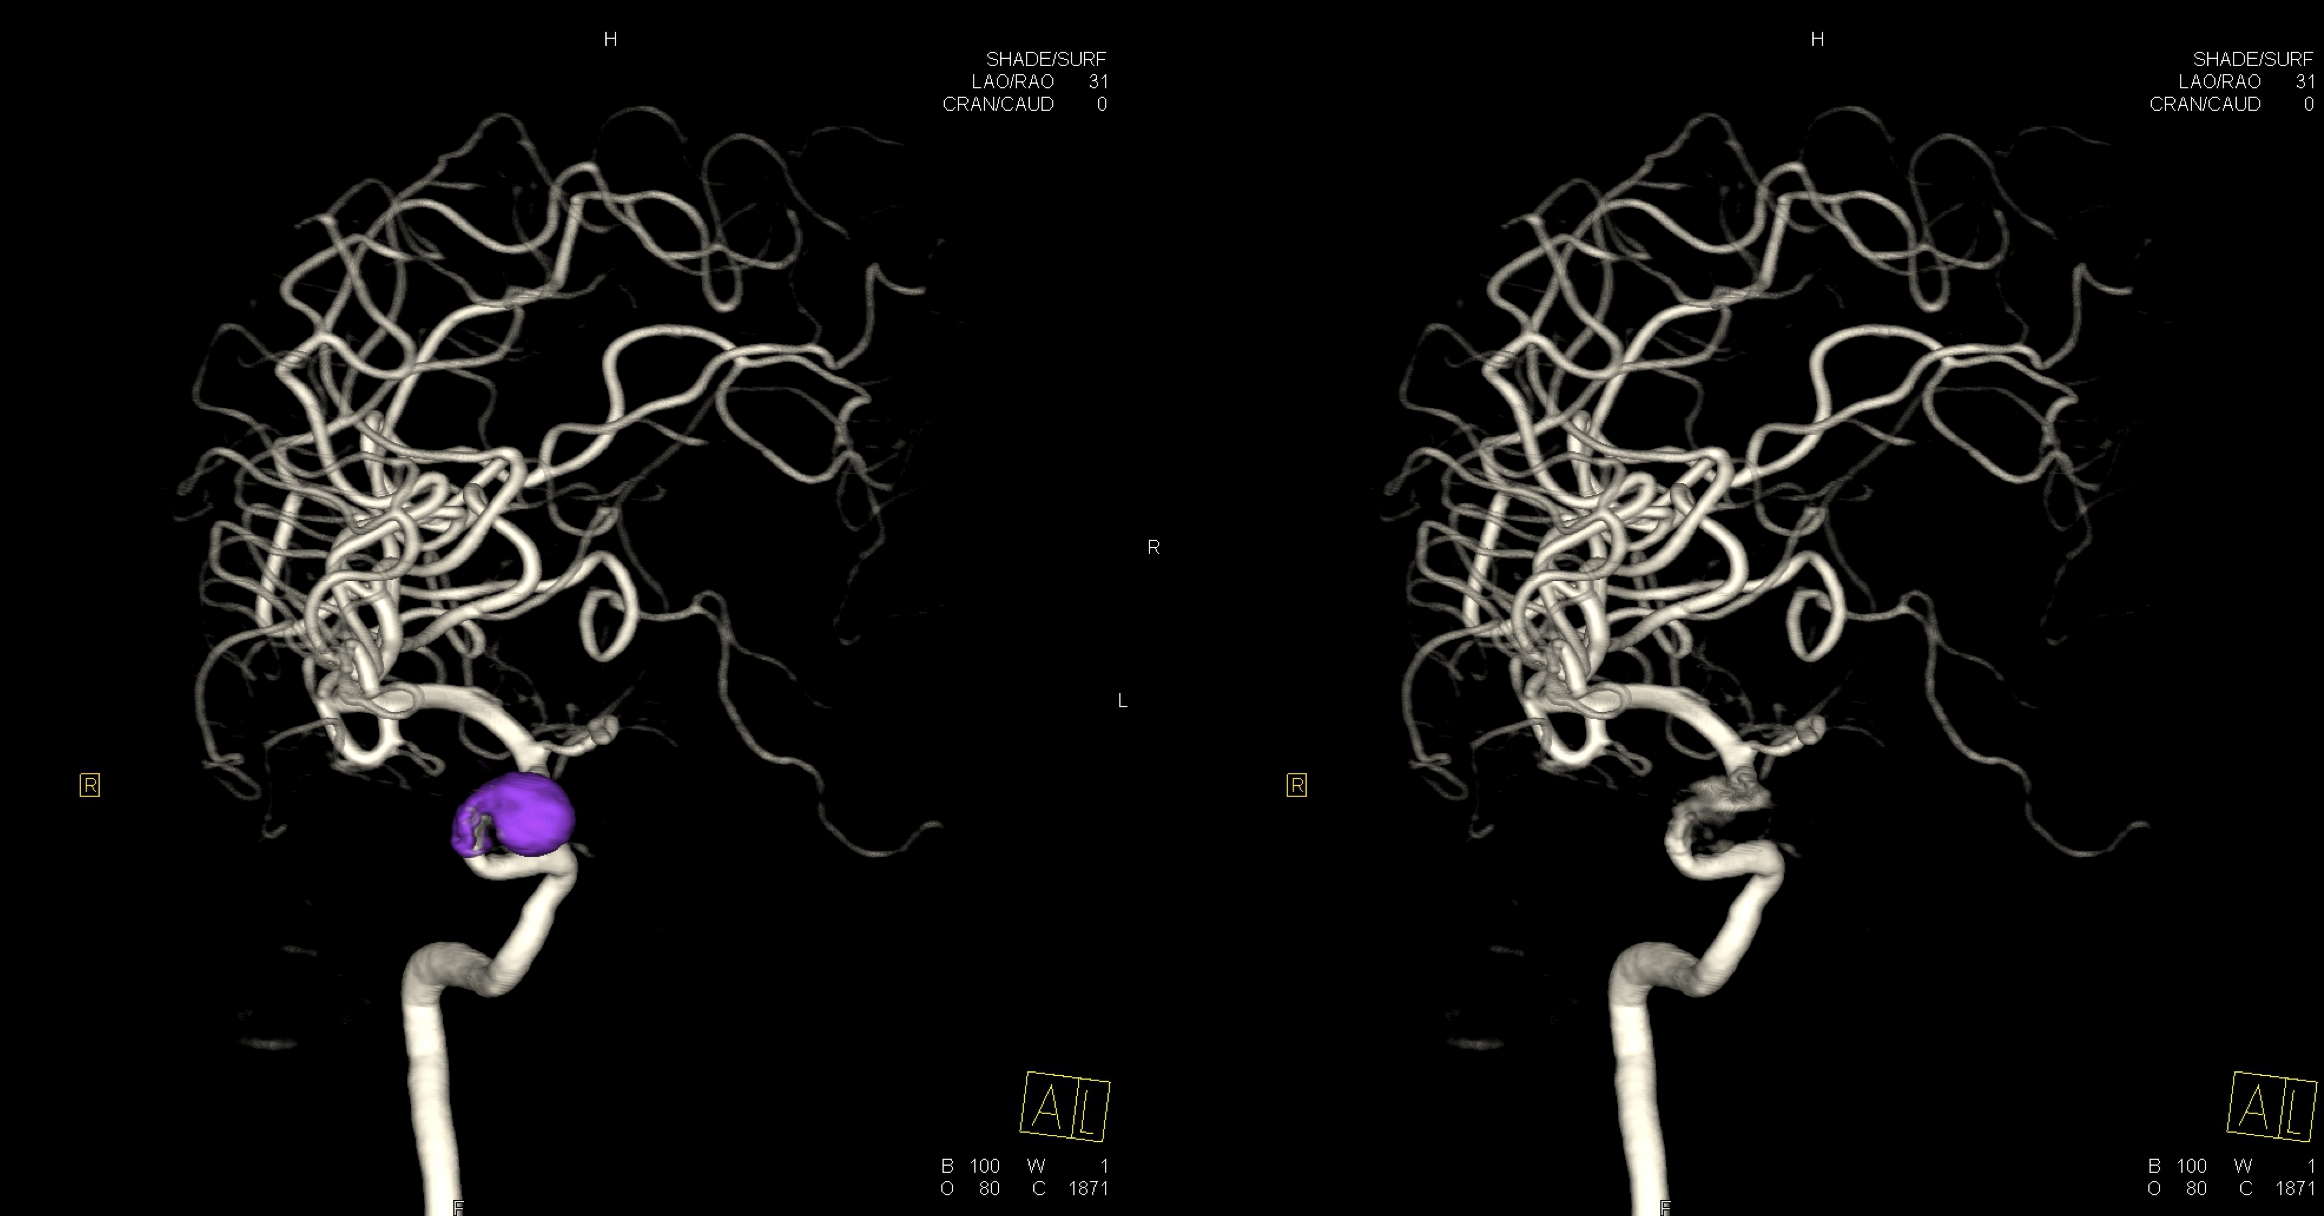

右侧颈内动脉三位造影重建:眼动脉段动脉瘤。给予支架辅助栓塞治疗。

右侧颈内动脉三维重建:动脉瘤未见复发,载瘤动脉通畅!

右侧颈内动脉三维重建:动脉瘤未见复发,载瘤动脉通畅!